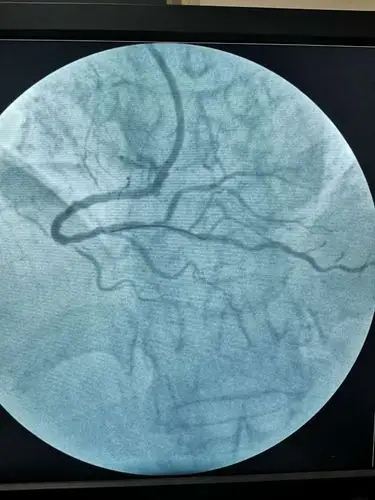

冠状动脉狭窄的血管造影

冠状动脉造影,左冠状动脉造影,左前降支狭窄.